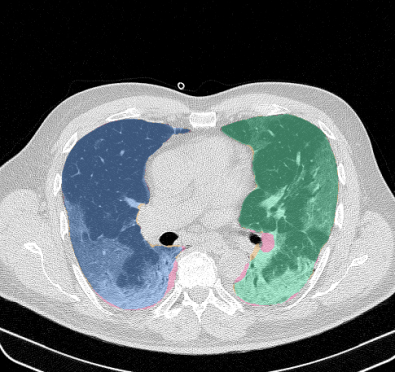

Lobar segmentation results for the proposed method and PTK are shown in Figure 5 for right lungs and Figure 6 for left lungs. For each image in the COVID-19 dataset (133 images in total), the lobar segmentation result was used to extract the amount of poor aeration () and consolidation () in each lobe. Common phenotypes of COVID-19 affected lungs were identified by hierarchical clustering over the fraction of poorly aerated and consolidated tissue in each lobe. Dendrographic analysis in Figure 7 reveals four primary clusters of patients that were identified by the hierarchical clustering: (a) mild loss of aeration primarily in the two lower lobes without consolidation; (b) moderate loss of aeration focused in the two lower lobes with or without consolidation in lower lobes; (c) severe loss of aeration throughout all lobes with or without consolidation; and (d) severe loss of aeration and consolidation throughout all lobes.

Lung segmentation results for the polymorphic and nonpolymorphic models are shown in Figure 3. Quantitative evaluation of lung segmentations was performed on CT images by comparing the segmentations to ground truth manual segmentations. The Dice coefficient was used to measure volume overlap and the average symmetric surface distance (ASSD) was used to assess boundary accuracy. The ASSD and Dice coefficient results for each of the four evaluation datasets are shown in Table 2. Overall, on the COVID-19 dataset the polymorphic model achieved an average ASSD of mm and average Dice coefficient of . By comparison, the nonpolymorphic model achieved an average ASSD of mm and average Dice coefficient of . ASSD and Dice coefficient results with respect to nonaerated lung volume fraction are displayed in Figure 4. Two-way analysis of variance revealed a significant interaction between model and nonaerated fraction for each evaluation metric, indicating that the regression coefficients with respect to nonaerated fraction were significantly different for polymorphic vs. nonpolymorphic models.